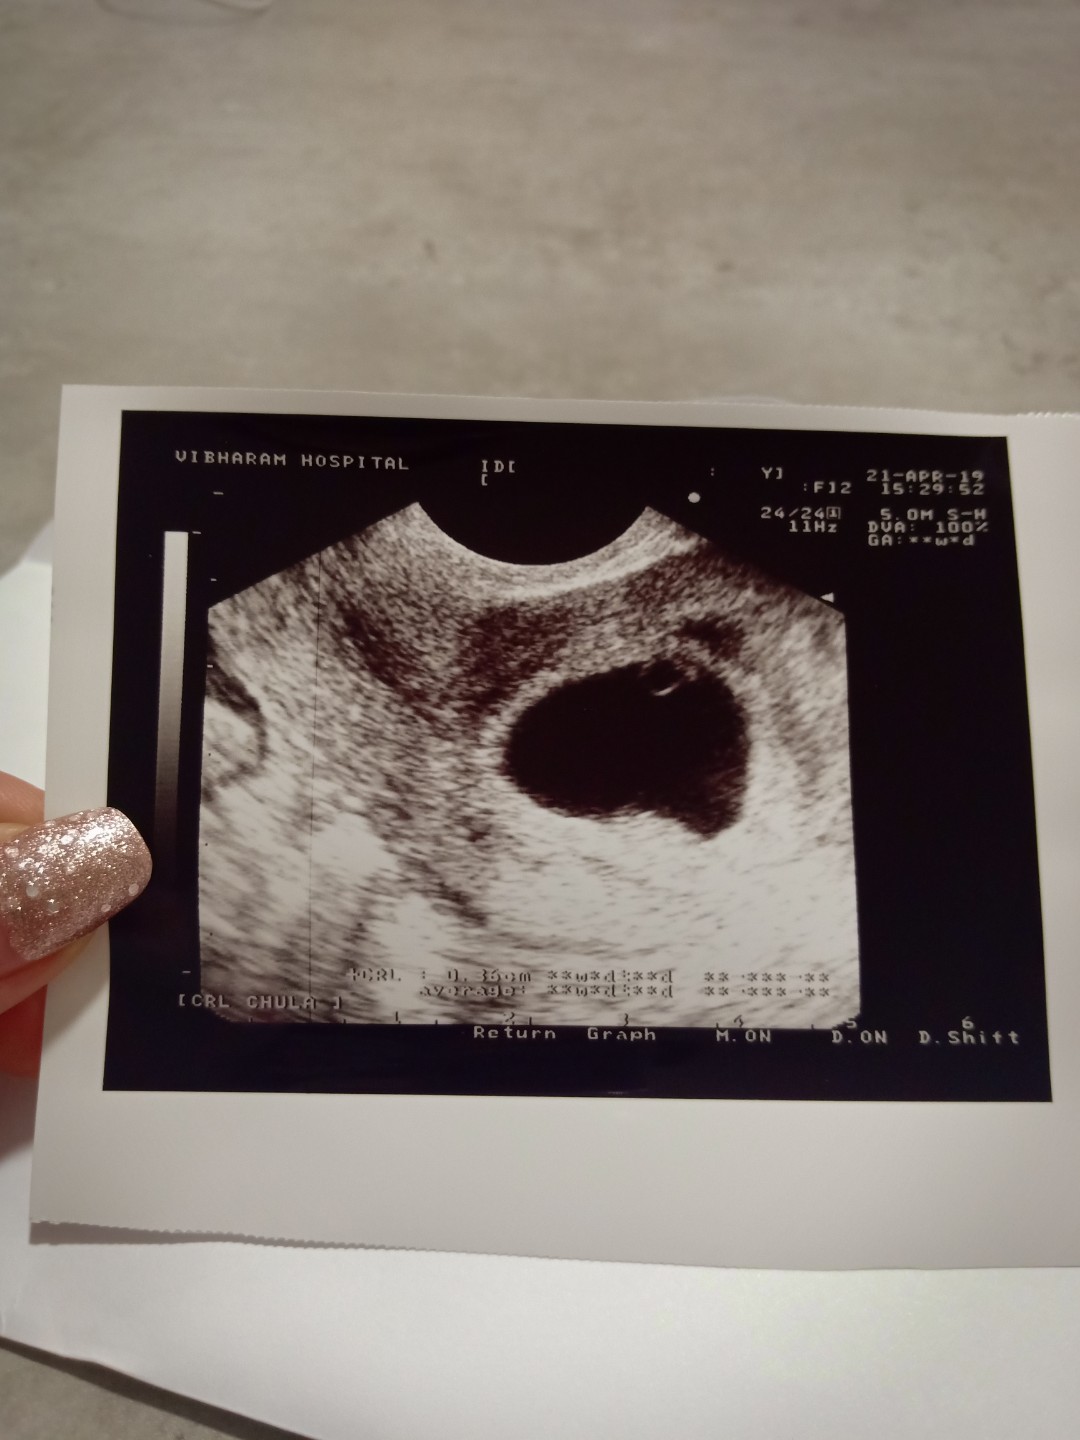

ภาพแรกเห็นแต่ไข่แดง กับหัวใจกระพริบจ้า